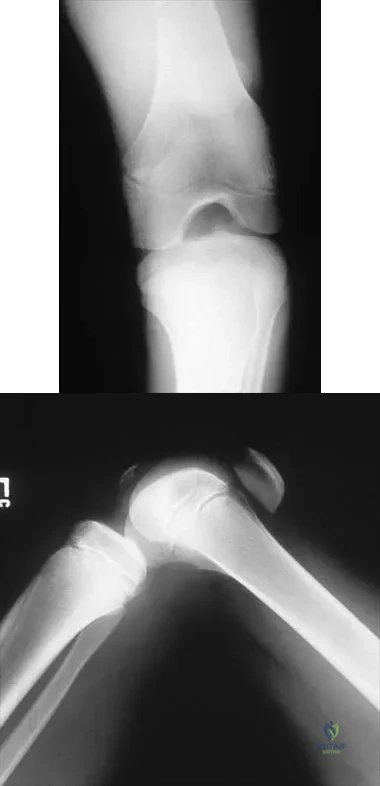

In performing an opening wedge high tibial osteotomy at the tibial tubercle, the osteotome extends 5 mm posteriorly and centrally out of the bone as shown in Figures 17a and 17b. What is the first structure it enters?

Explanation